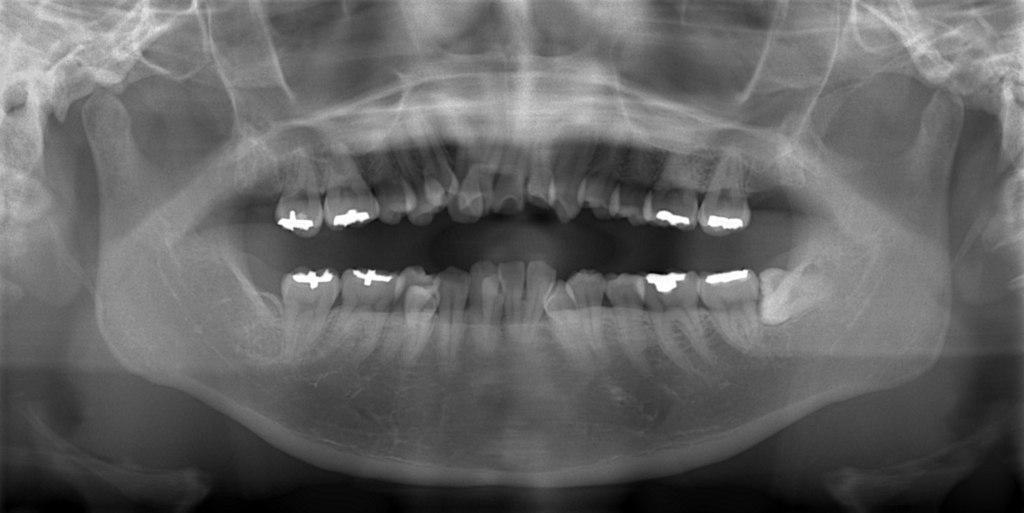

レントゲン写真で確認すると、

この患者さんの場合、

矯正後の状態をレントゲン写真で確認すると、

では、矯正治療前後の「レントゲン写真」や「歯並び」「横顔と口元の写真」などを比較してみましょう。

まずはレントゲン写真の比較です。

左側が矯正治療前、右側が矯正治療後